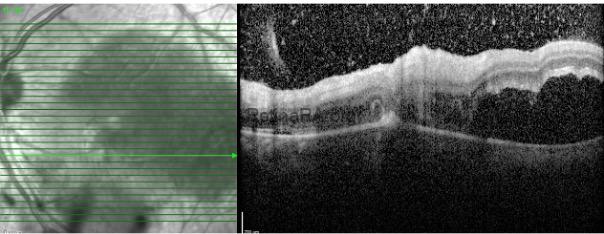

A 23y old, female patient presented with decreased vision in her left eye. Best corrected visual acuity levels were 1.0/CF 5, intraocular pressures were within normal limits, and there was 1+ anterior chamber reaction in her left eye. On fundus examination, while the right eye was normal, a hyperpigmented scar and active lesion were observed near the fovea in the left eye. There was involvement of the arteries adjacent to the lesion.

OCT showed intravitreal hyperreflective spots concentrated on the lesion, full-thickness retinal involvement, and serous retinal detachment.